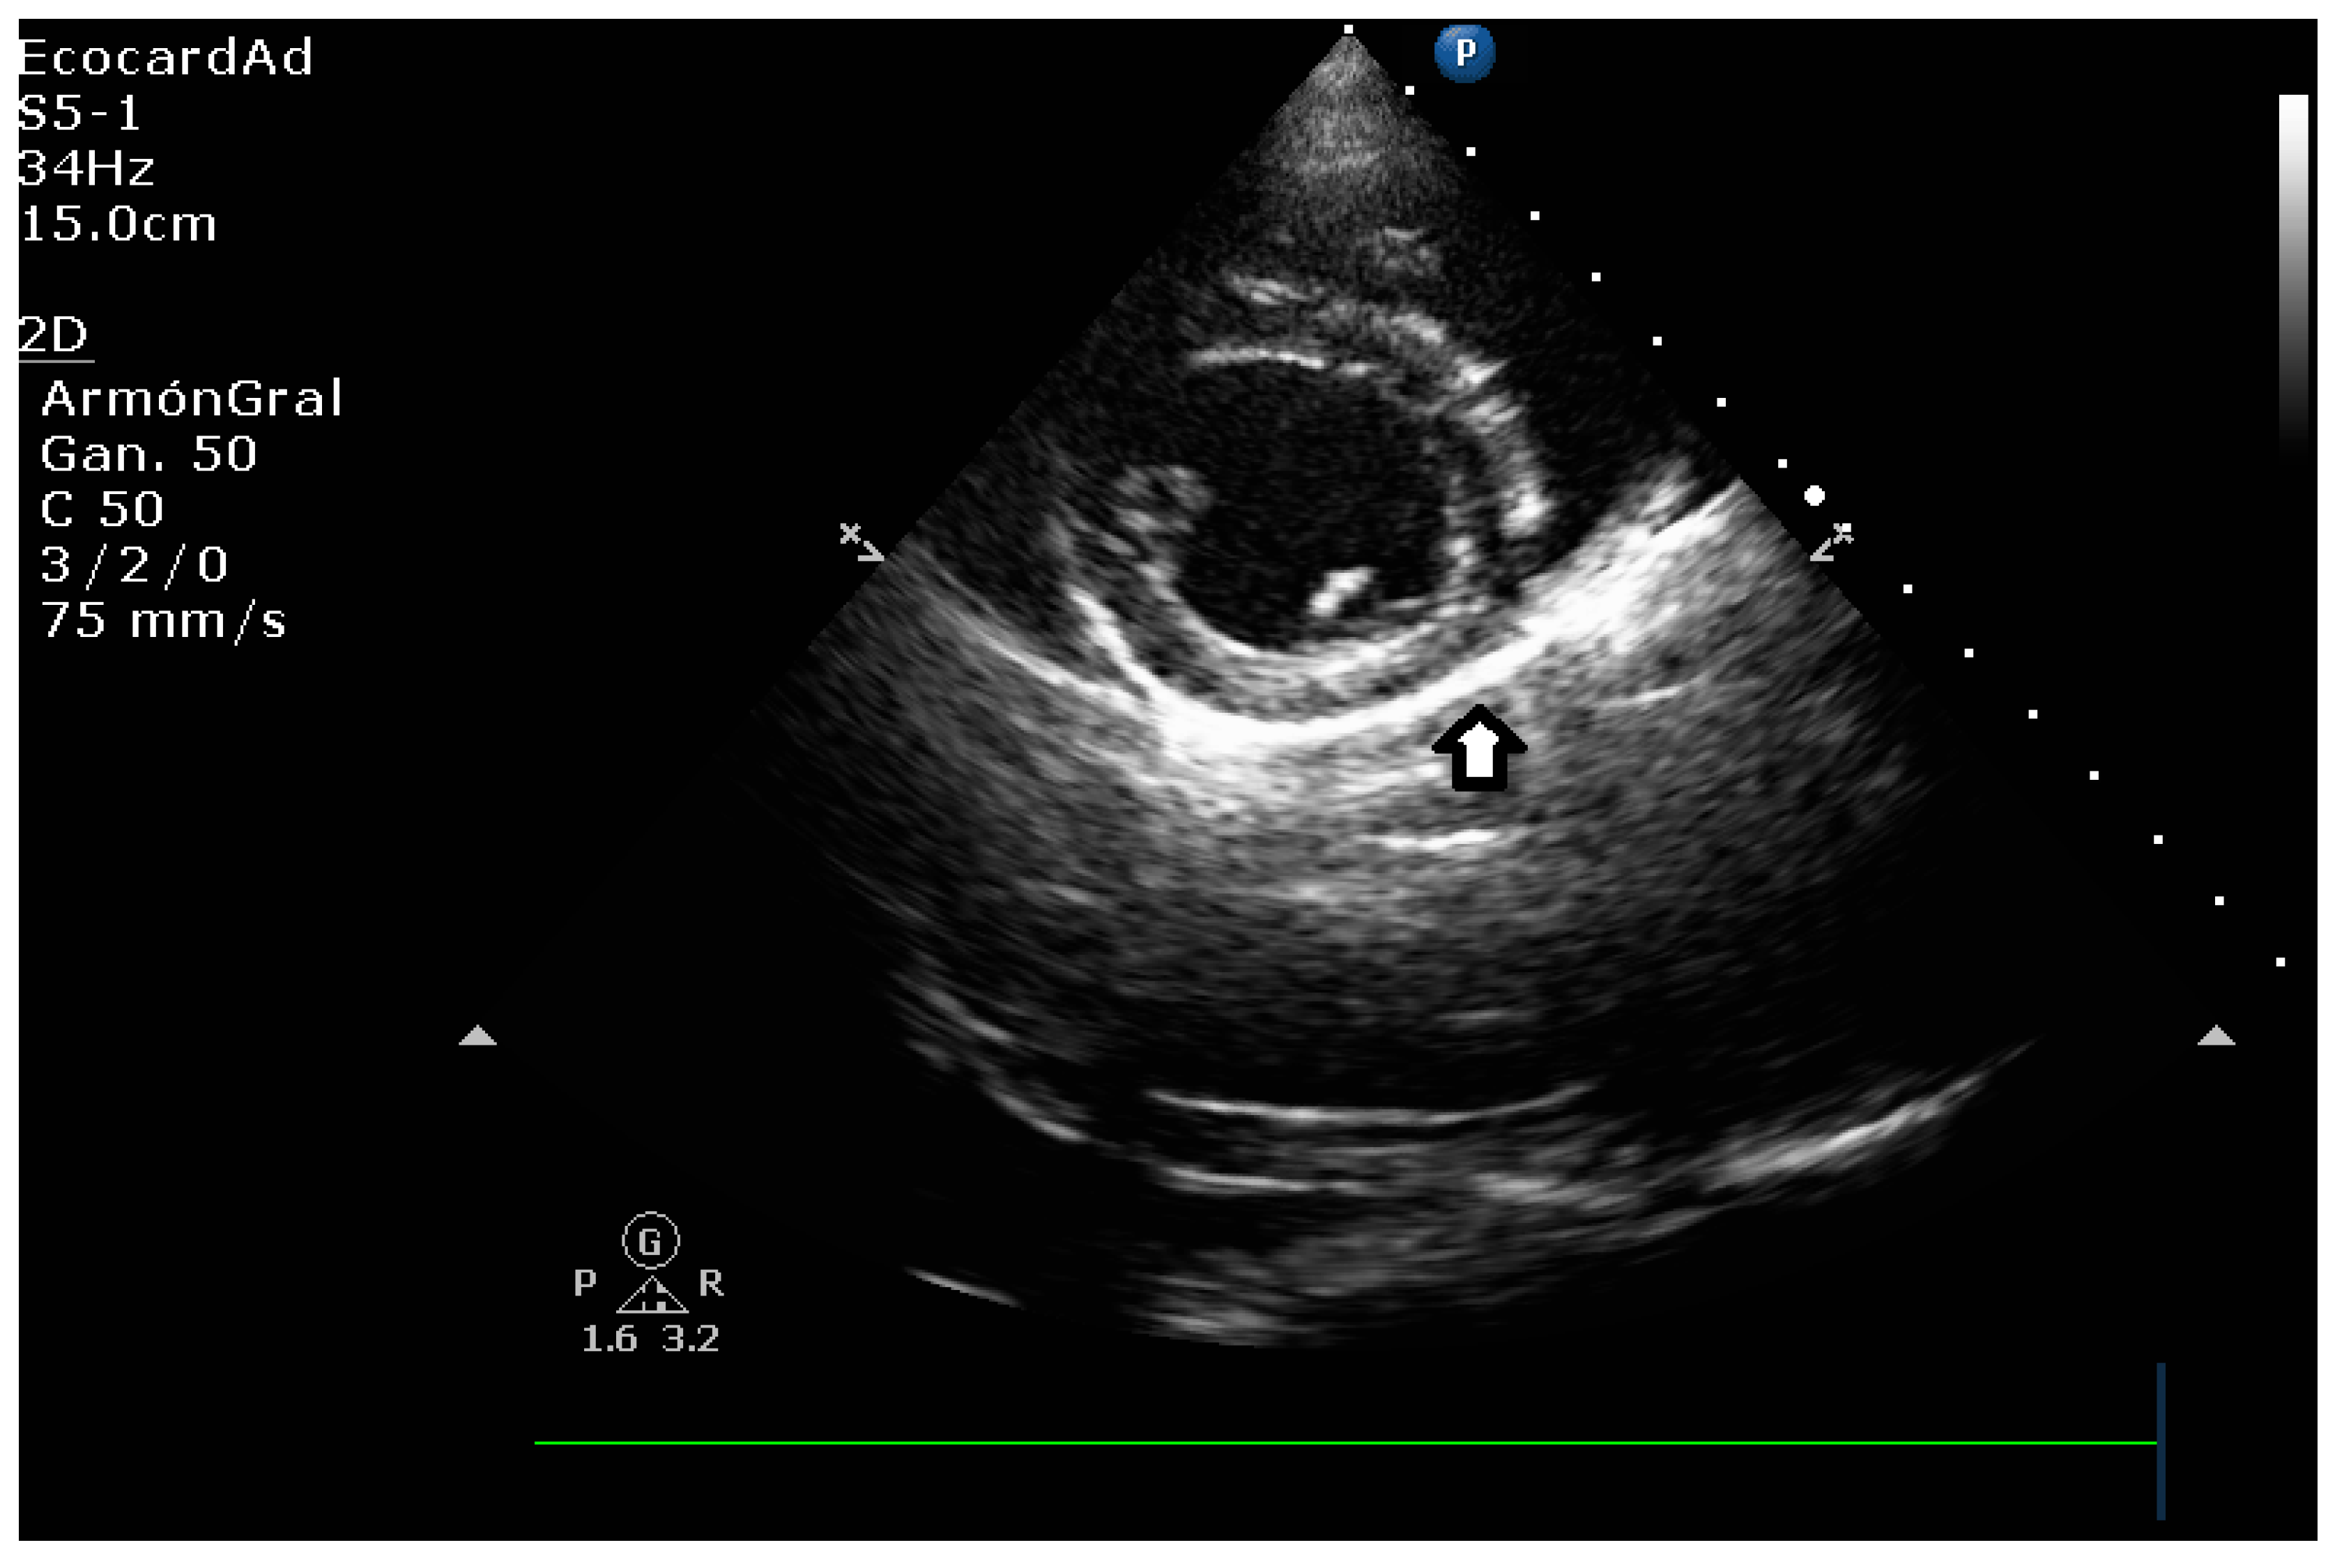

4.3. Canine Myxomatous Mitral Valve Disease. Comparative Transthoracic Echocardiography with Human Mitral Valve Prolapse

4.6. Left Heart Remodeling Assessment and LA Evaluation

4.8. Key Main Useful Echocardiographic Considerations for the Approach of Mitral Endocardiosis in Canine Patients

4.8.1. Evaluation of the Regurgitant Area

4.8.3. Degree of Myxomatous Degeneration

4.8.4. Mitral Valve Prolapse